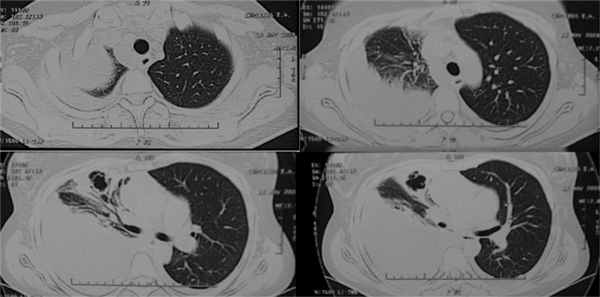

Во II стадии туберкулезной эмпиемы изменяются состав и консистенция плеврального выпота. Если в начале этой фазы выпот довольно жидкий, фибрина еще мало, а спайки нежные и эластичные, то можно довольно легко достичь полного расправления легкого и соответственно выздоровления путем активного дренирования плевральной полости. Если процесс зашел далеко и фибринозно-гнойное содержимое плевральной полости начало организовываться, появилось утолщение плевры и легкое не расправлено, то шансы на выздоровление путем местной санации плевральной полости невысоки (рис. 2). Рис. 2. Компьютерные томограммы органов грудной клетки пациента во II стадии туберкулезной эмпиемы. Отмечается утолщение париетальной плевры, сгущение экссудата, пневмофиброз в легком.